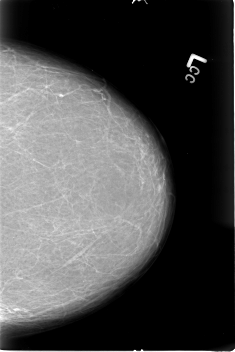

B_3022_1.LEFT_CC

LEFT_CC LINES 4568 PIXELS_PER_LINE 3048 BITS_PER_PIXEL 12 RESOLUTION 50 NON_OVERLAY

LEFT_MLO LINES 4736 PIXELS_PER_LINE 3016 BITS_PER_PIXEL 12 RESOLUTION 50 NON_OVERLAY